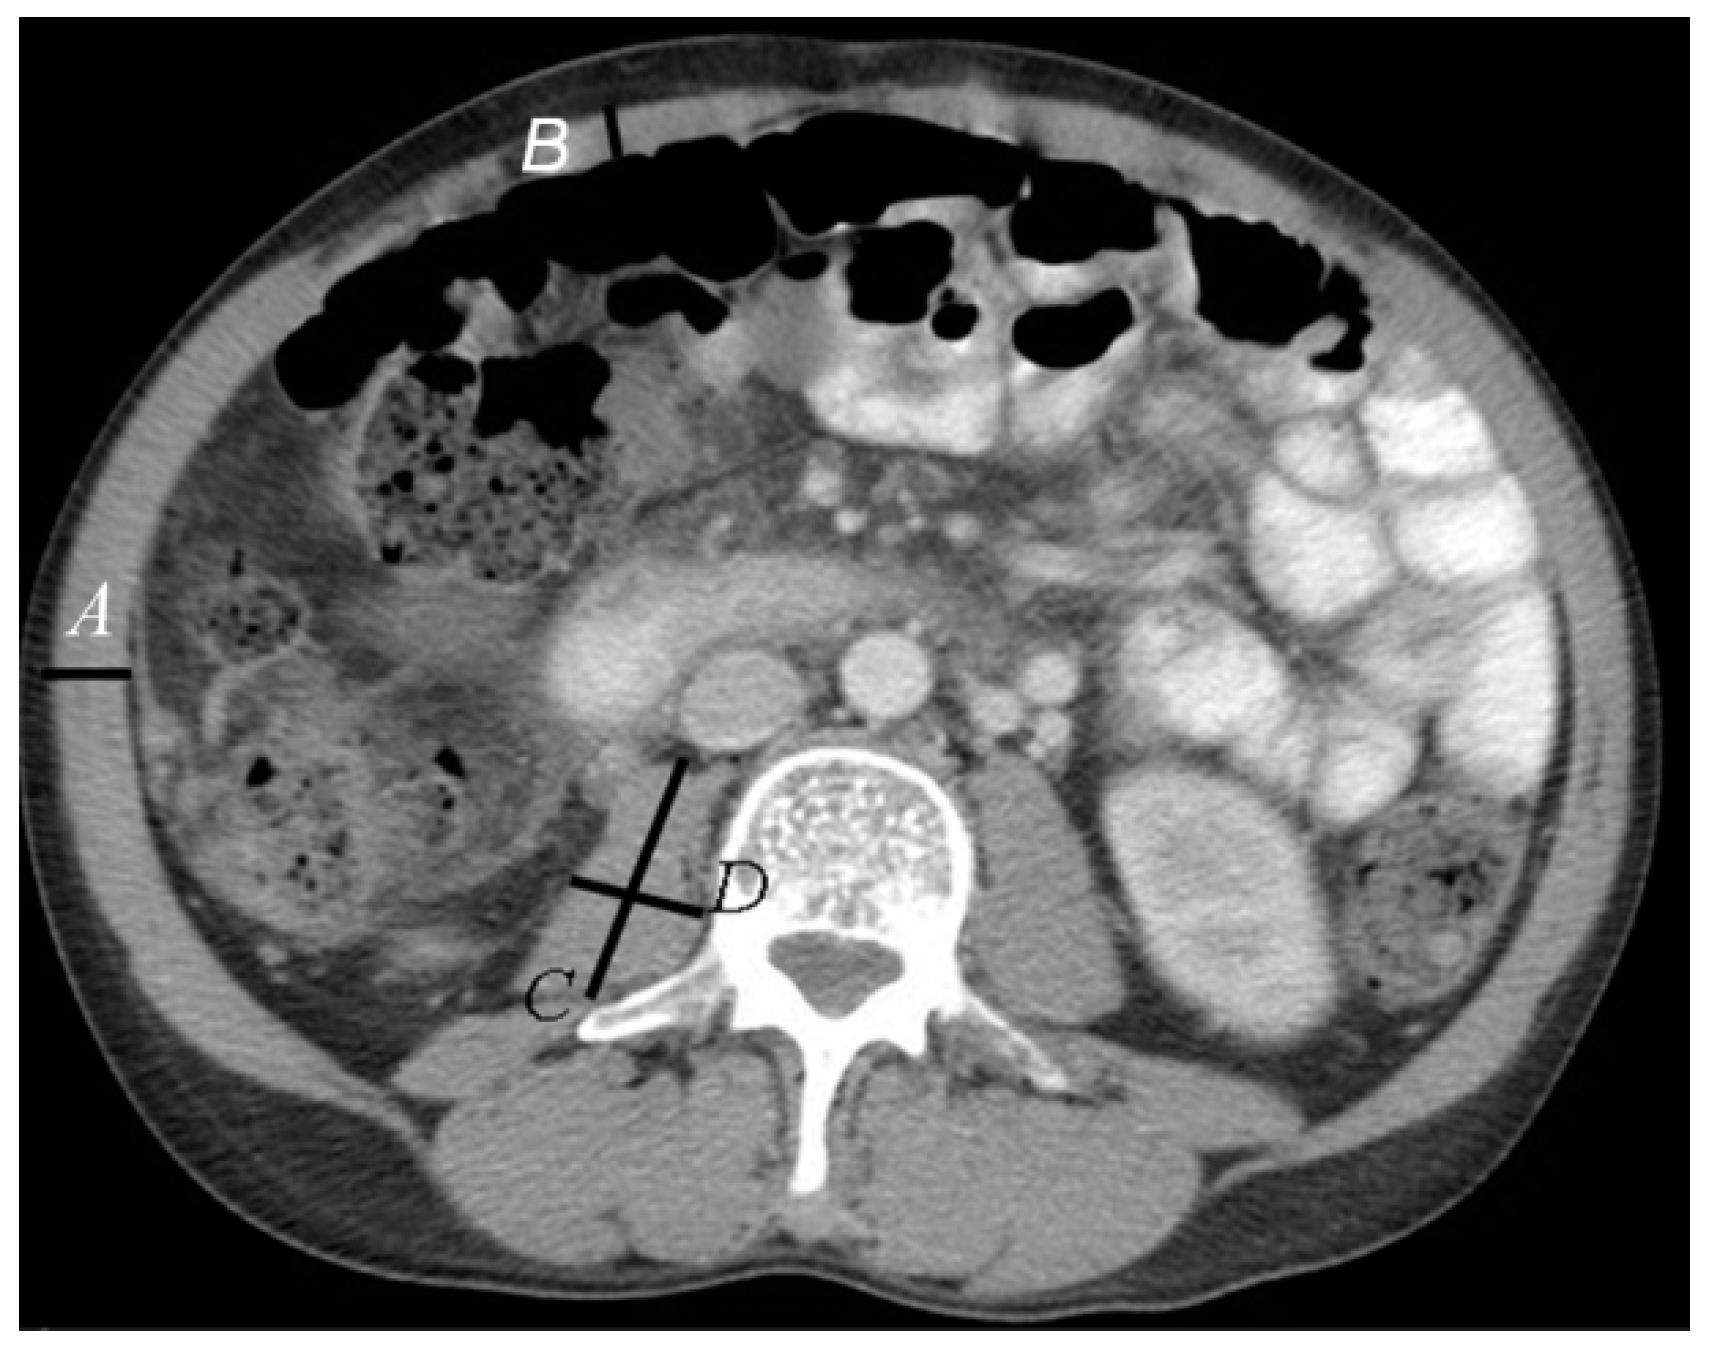

| Corrected psoas muscle area (mm2/m2) (mean ± SEM) | 301.1 ± 7.5 | 273.4 ± 6.0 * | 483.8 ± 15.5 * |

| Psoas muscle area (mm2/m2) (SEM) | 275 ± 6.0 | 484 ± 15.5 | 0.97 (0.59–0.980) | <0.0001 |